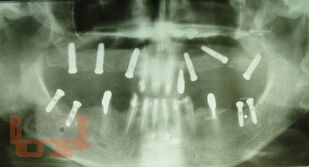

В учебном пособии рассматриваются вопросы клинико-рентгенологической диагностики хирургических осложнений дентальной имплантации, возникающие в интраоперационном и раннем послеоперационном периодах. Разделы пособия содержат клинические примеры осложнений, возникающих на хирургическом этапе имплантологического лечения больных. В отдельной главе, посвященной социологическому исследованию, приведены данные анкетирования врачей-стоматологов по проблемам имплантологического лечения, которые позволяют выявить наиболее острые проблемы, стоящие перед имплантологами, в том числе, пробелы в послевузовском образовании. Пособие иллюстрировано цветными фотографиями, облегчающими восприятие излагаемого материала.